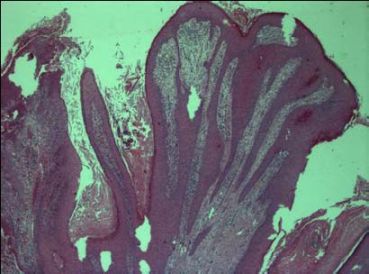

Třetí diagnostická explorace byla provedena koncem července a zaslána prof. MUDr Michalovi, FN Plzeň. Verukózně konfigurovaný tumor byl vzhledem k absenci atypií a atypických mitóz uzavřen jako condyloma accuminatum(Obr.3)

Obrázek 3

V diferenciální diagnostice patologem zmíněn verukózní karcinom, stejně jako možnost častých recidiv a pozitivity HPV.